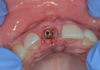

L'intervention se fait sous anesthésie locale, avulsion atraumatique de la dent 11 et pose d un implants straumann 4,1X16 BLT SLACtive.

Le couple d insertion est de 50N/CM.

Une empreinte est réalisee.

La prothèse provisoire est réalisée le jour même par le laboratoire ARV, son couple d insertion est de 35N/Cm